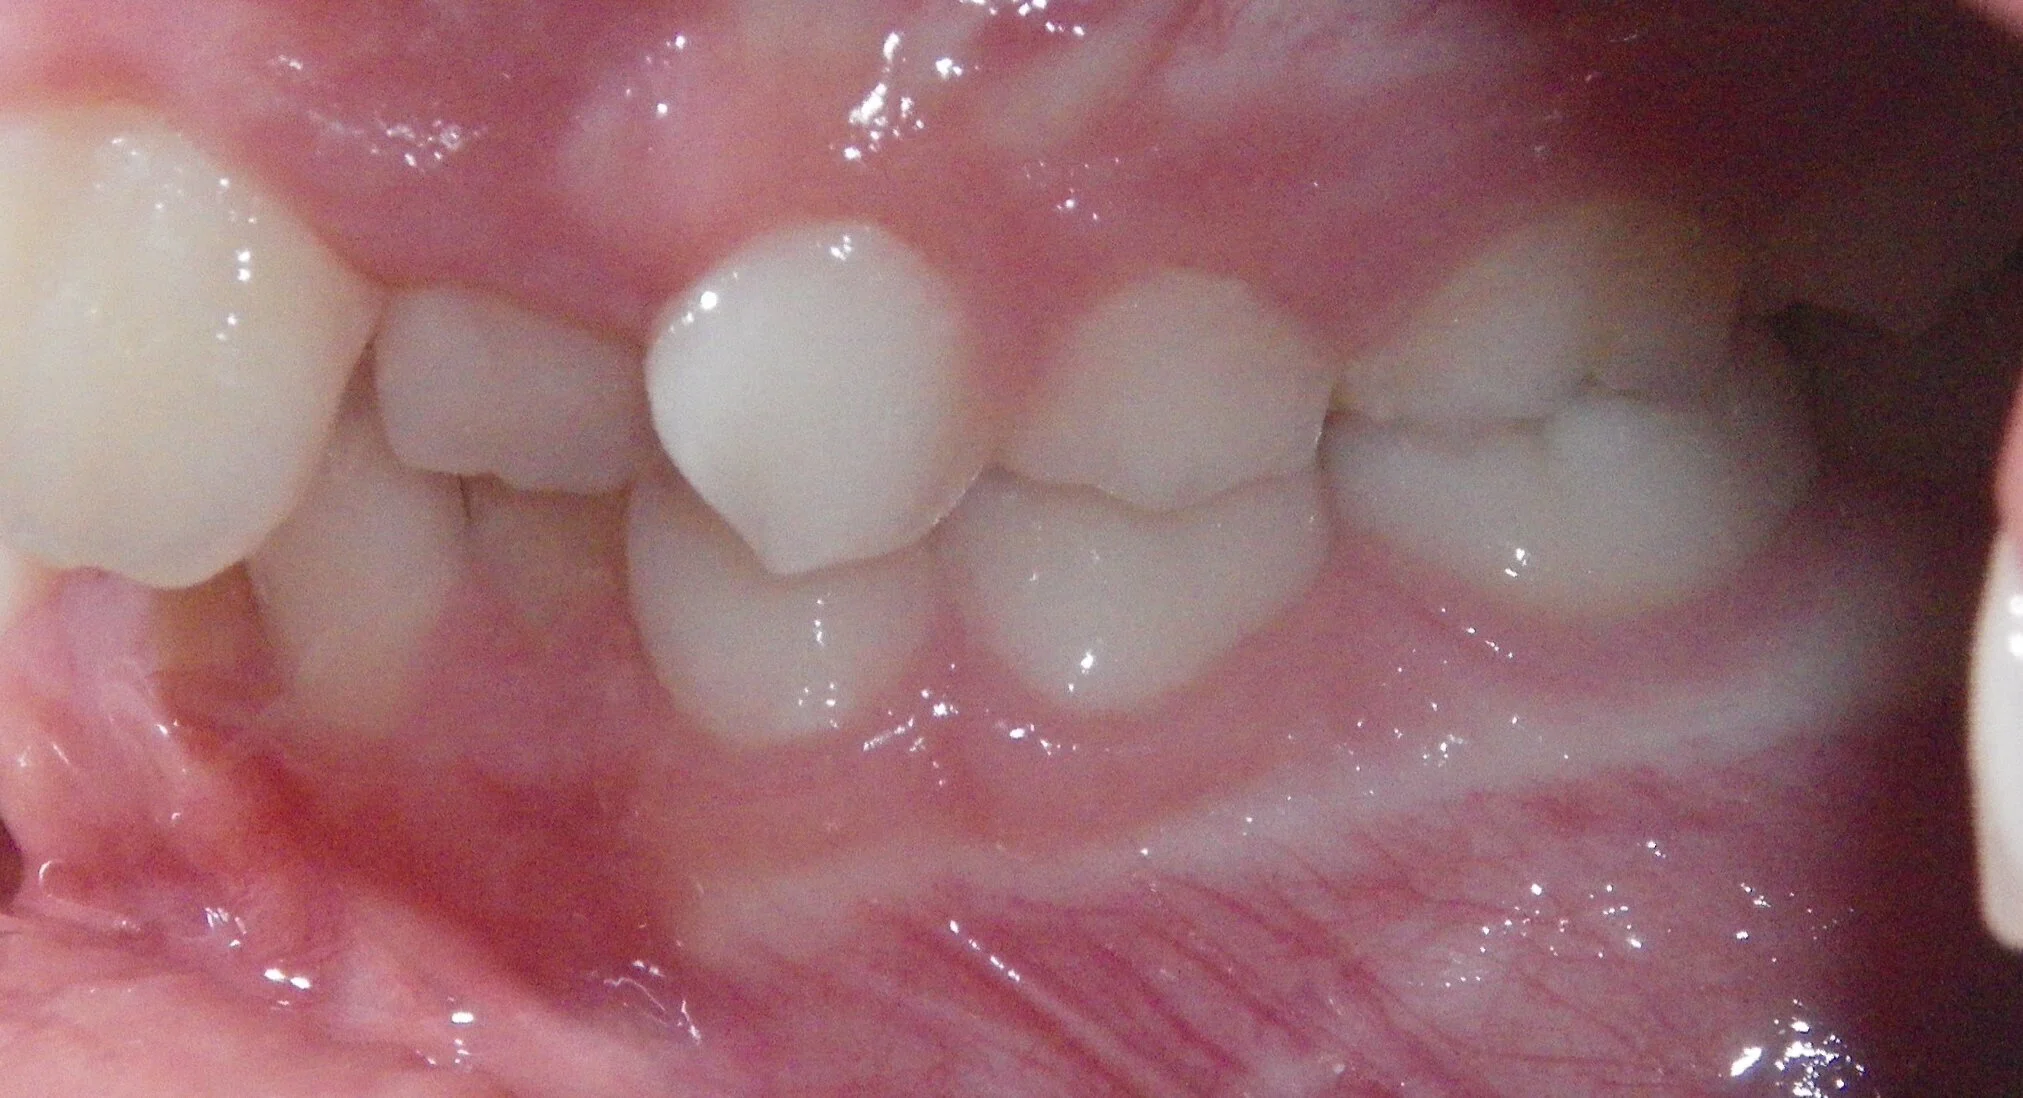

Phase I can be used to help change unfavorable growth or to make room so all the adult teeth have room to erupt. Here, we used Phase I to make room for the adult canines and followed up with Phase II treatment to a get a great esthetic and functional result!